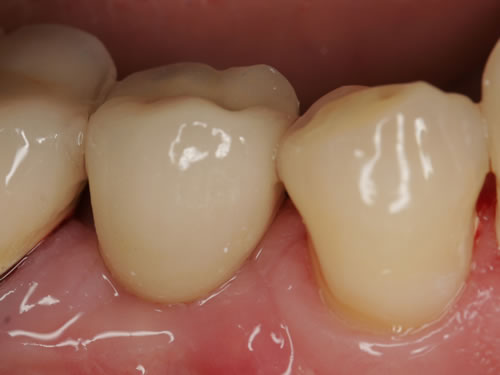

3.5 Reduzierte Bezahnung

Bei einer Einzelzahnlücke handelt es sich um eine zahnbegrenzte Lücke, bei der nur ein Zahn fehlt. Häufig sind die Nachbarzähne kariesfrei und nicht überkronungsbedürftig oder schon mit Zahnersatz versorgt, so dass eine Implantatversorgung eine sinnvolle Alternative zur konventionellen Brücke ist (Abb. 3.28, 3.29).

Abb. 3.28: Einzelzahnlücke im Unterkieferseitenbereich mit eingesetztem Implantat.

Abb. 3.29: Zementierte „unsichtbare“ Implantatkrone.